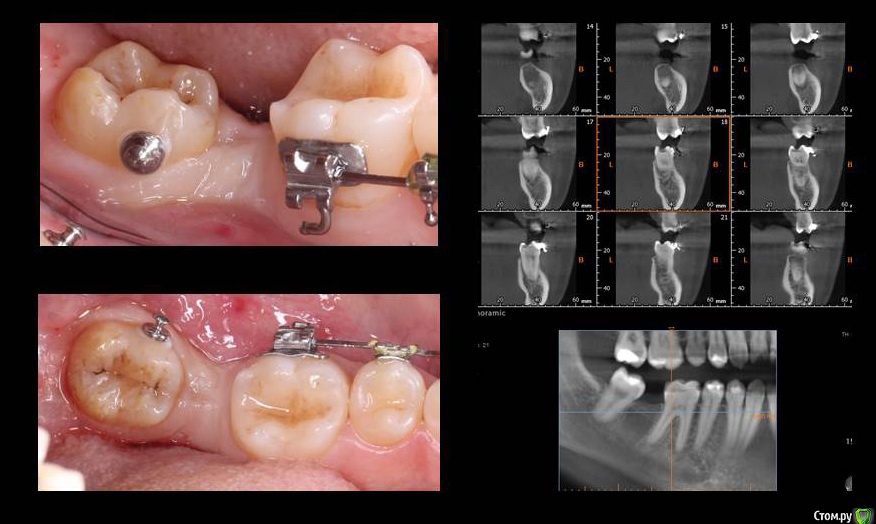

колесников Опубликовано 24 июля, 2018 Поделиться Опубликовано 24 июля, 2018 Прошу дистализировать 8ку и ставлю профайл 4.5х9 +сст 1 Ссылка на комментарий

Neilrus Опубликовано 24 июля, 2018 Поделиться Опубликовано 24 июля, 2018 (изменено) мне кажется в вопросе подвох.Вижу два варианта или мезиализировать (что тяжко и не факт) или дистализировать ортовинтом и через пару мес после имплантат Изменено 24 июля, 2018 пользователем Neilrus 1 Ссылка на комментарий

Aquarius Опубликовано 24 июля, 2018 Поделиться Опубликовано 24 июля, 2018 Предположу ,что все таки дистализация , раз кнопка уже приклеена. 1 Ссылка на комментарий

chervoncevdaniil Опубликовано 24 июля, 2018 Поделиться Опубликовано 24 июля, 2018 Почему такое желание сохранить эту восьмерку?Я так понимаю,что даже если она успешно дистализируется,то контакт будет только на медиальной ямке с верхним 7 1 Ссылка на комментарий

Bier Опубликовано 25 июля, 2018 Автор Поделиться Опубликовано 25 июля, 2018 Ситуация через 2 месяца 6 Ссылка на комментарий